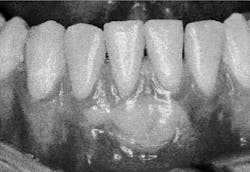

- Toothbrush abrasion. A hard bristle toothbrush or aggressive brushing can result in recession. Gingival tissues can be abraded over a period of time and can lead to root sensitivity. Photograph #3 provides an example. In this case, continued brushing with a hard toothbrush abraded away the gingiva as well as some root structure.

Photograph #4 is the same patient seen in photograph #2, six months after placement of a free gingival graft.

Photograph 3: Toothbrush abrasion

Photograph 4: Gingival augmentation, tooth #25